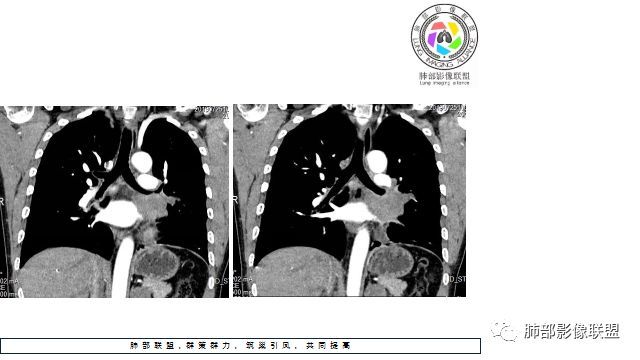

1.左下肺门区巨大肿块,支气管显示不清,轻度阻塞性炎症,没有明显肺不张,提示管腔受压狭窄可能性大于堵塞,这较少见于鳞癌。

4.病灶内有肺动脉走形,血管局部受压,未见破坏,病灶乏血供,呈血管包埋或血管造影征;侵袭性力强及破坏力弱、血管漂浮都符合SCLC,所以鳞癌的可能性也不大。

5.左肺门块影或淋巴结肿大,竭力挤兑肺门血管结构,呈冰冻肺门;有时候SCLC可以单独呈现冰冻肺门,而没有没有冰冻纵隔。

7.须特别注意的是,肺门区的融合块影,不排除它可能仅仅为转移淋巴结。